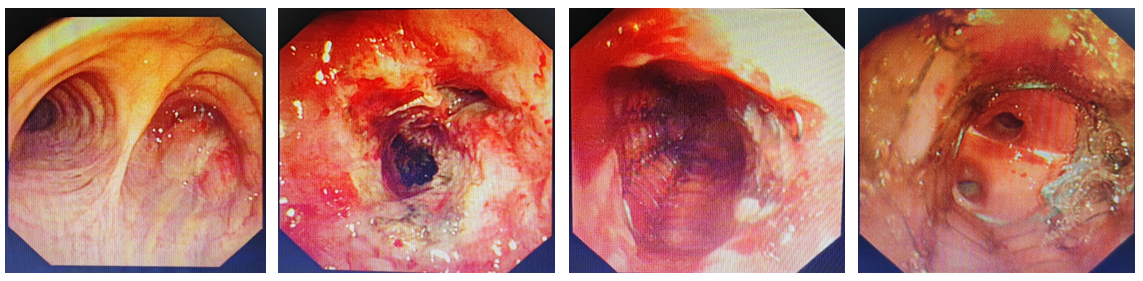

“必须立即架起‘生命桥梁’!”经家属同意后,于世寰主任当机立断,决定实施支气管镜下肿瘤清除+气道支架植入术。11月17日,这场与死神赛跑的“生命突围”在介入中心展开。支气管镜传回的影像中,肿瘤组织已将气道完全侵占,这属于 “完全性堵塞” ,是医学上最危急的情况之一。团队手中的内镜器械成为开辟通路的“精密武器”。

在麻醉科刘淑杰副主任保驾护航下,董福实副主任医师和吴昊岚主管护师合作默契,高频电圈套、氩气刀率先切割肿瘤组织,瞬间汽化开辟空间;冷冻探头将瘤体冻结黏连,取出时出血极少;最后,由活检钳将病灶精准钳取。通过“冷热交替”的微雕式操作,在毫米间为生命开辟通路。

图2 第二次支气管镜下介入治疗后,放置气道支架

通路打通后,于世寰主任精准测量狭窄段长度,一枚40mm×12mm的镍钛合金支架被送入气道。在体温作用下,这枚“记忆金属”支架缓缓张开,完美贴合支气管壁,稳稳撑起呼吸通道。